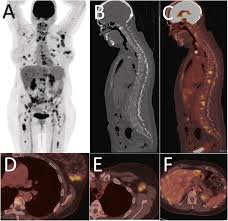

Best FDG PET CT Scan in Green Park